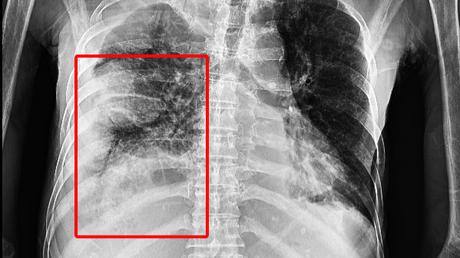

Sau khi xét nghiệm và thực hiện các cận lâm sàng cần thiết, phát hiện tình trạng tràn mủ phổi phải cùng nhiều ổ áp xe, đông đặc thùy dưới phổi trái, chẩn đoán bệnh nhân bị hôn mê CRNN - suy hô hấp cấp, các bác sĩ đã tiến hành cấp cứu rồi chuyển lên điều trị tại khoa Hồi sức tích cực - Chống độc.

Tại đây, mặc dù các bác sĩ đã tiến hành đặt ống nội khí quản, hỗ trợ thở máy, góp phần cải thiện chỉ số oxy trong máu (Sp02) lên khoảng 88-90%, nâng áp lực dương cuối thở ra (Peep) lên cao nhưng phổi của bệnh nhân vẫn không nở đều. Kết quả chụp CT-Scanner 32 cho thấy hình ảnh tràn dịch khoang màng phổi hai bên gây xẹp thụ động nhu mô phổi lân cận, giãn các nhánh phế quản phải trong vùng nhu mô phổi xẹp. Xuất hiện hạch trung thất và hạch hố thượng đòn phải. Tiên lượng tử vong cao nếu không khẩn trương xử trí sạch ổ cặn, kích phổi phải giãn nở tốt đáp ứng thông khí.